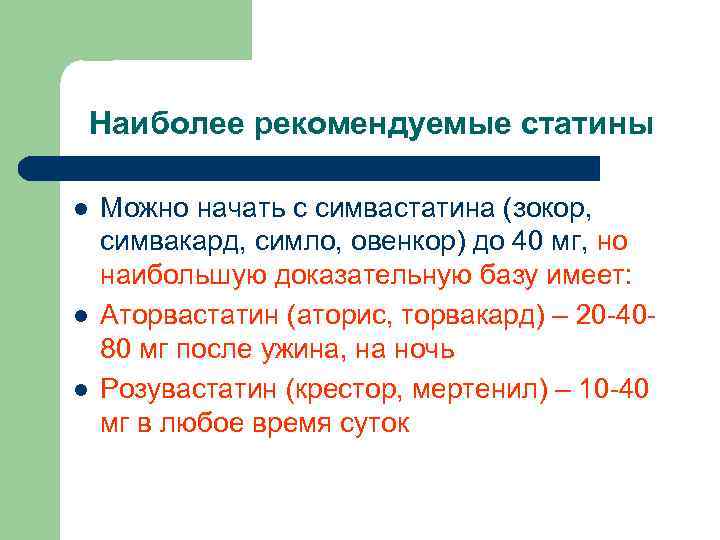

Наиболее рекомендуемые статины l l l Можно начать с симвастатина (зокор, симвакард, симло, овенкор) до 40 мг, но наибольшую доказательную базу имеет: Аторвастатин (аторис, торвакард) – 20 -4080 мг после ужина, на ночь Розувастатин (крестор, мертенил) – 10 -40 мг в любое время суток